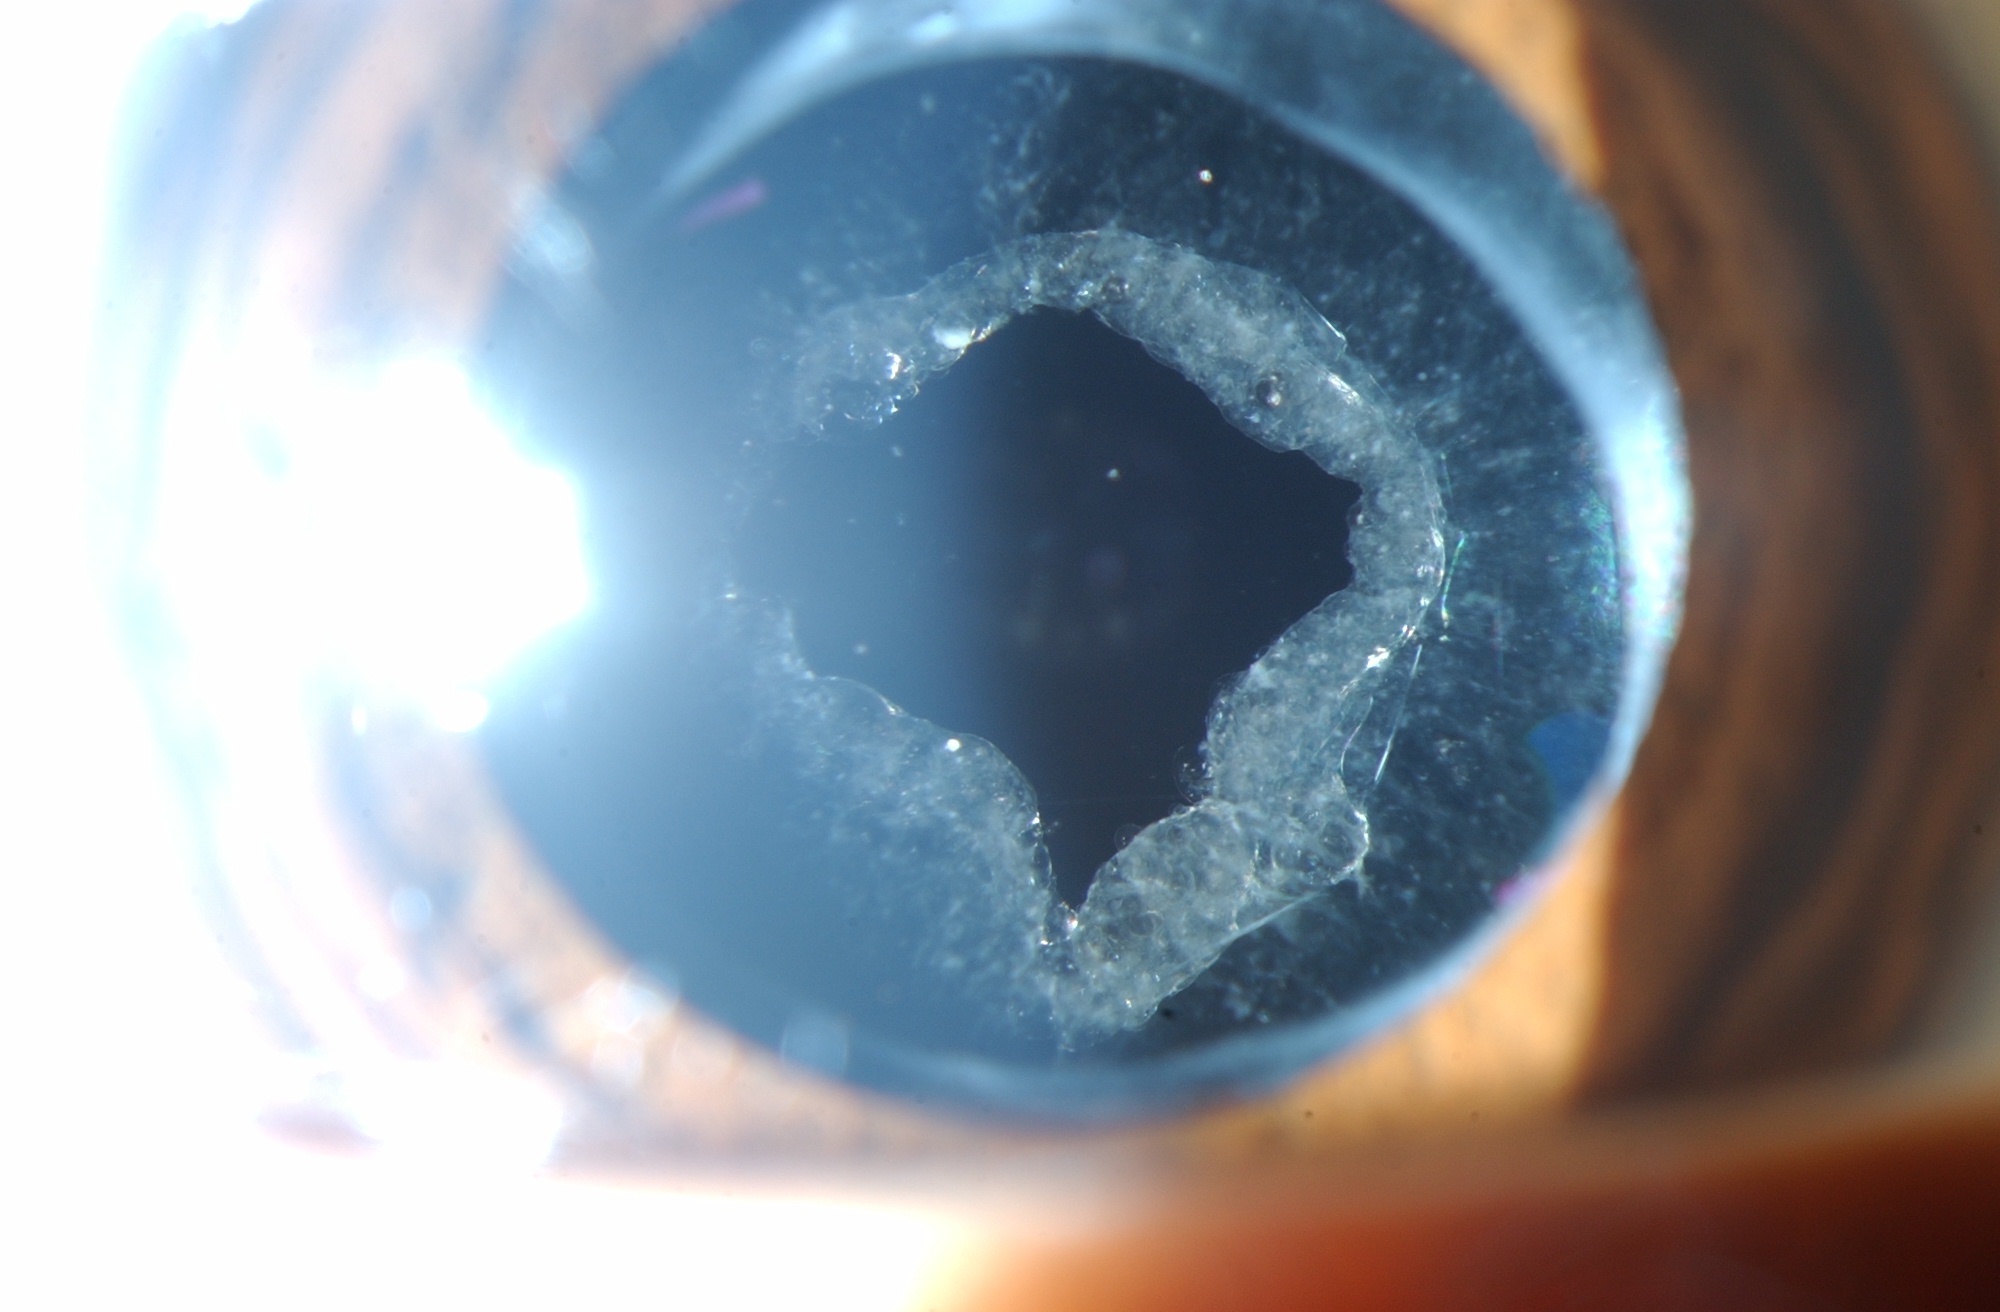

Showing post NDYAG laser anterior capsulotomy opening. A clear central Post Op Yag Capsulotomy Posterior capsule opacification can threaten vision postoperatively, but this can be avoided simply with a yag capsulotomy. Yag laser capsulotomy is a procedure used to treat a condition called posterior capsule opacification (pco), which can occur after. A yag laser posterior capsulotomy is a procedure done to help remove scar tissue after you’ve had a lens. The aim of this. Post Op Yag Capsulotomy.